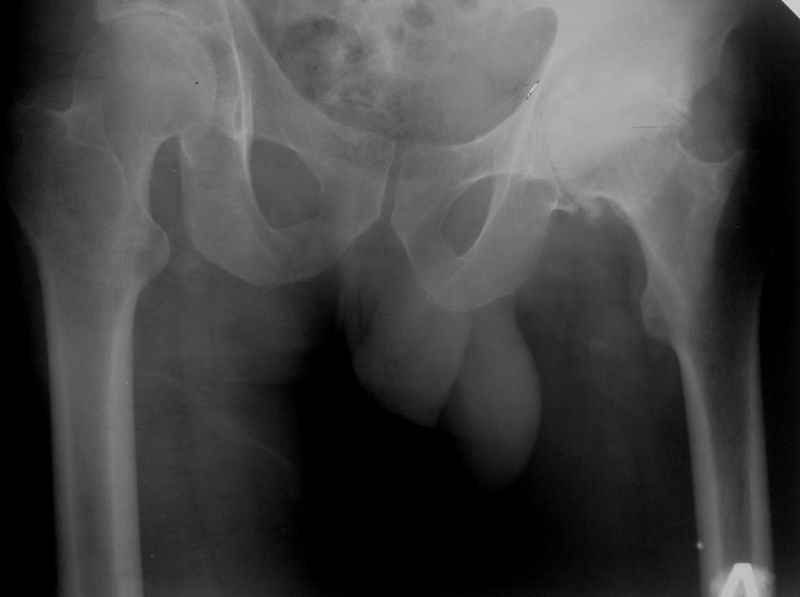

Исходный сустав в приложении.

Хотелось бы увидеть рентгенограмму до имплантации. Погружение достаточное, хороший контакт с костным ложем. Центр вращения сустава сохранен. Мне кажется выбрана большая "чашка". Во всяком случае - не стоит ничего менять. Канзюба А.И.

Исходная рентгенограмма?

Исходная R- гр см. выше.

У меня опыт по эндопротезированию совсем небольшой. Еще 5 лет тому назад у нас в городе не было протезирования. Во вложении снимки одного больного из нашего города. который оперировался в 1999 году в Южной Корее. разница по времени замены второго сустава 11 дней. Больной по настоящее время ходит без проблем, особых жалоб не предъявляет, весит он 98 кг. Может быть есть смысл подождать, по наблюдать а оперировать никогда не поздно.